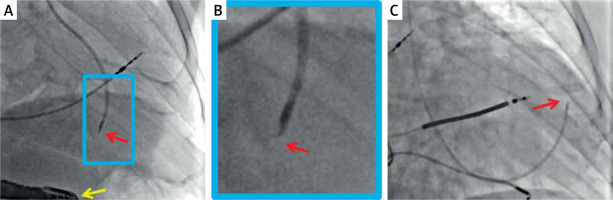

The idea to directly implant cardiomyocytes into the injured area was initially tested in animal models. Contrary to adult cardiomyocytes, which did not survive under any conditions, fetal and neonatal cells formed new and mature myocardium in inbred rats [25]. The procedure can be done either under direct vision, usually using minimally invasive surgical access (Figure 1 C) or percutaneously (Figure 2).

Figure 2

Typical radiographic images of percutaneous trans-endocardial delivery of stem cells using a dedicated, steerable catheter with a curved needle (red arrow) that has an adjustable length and possesses side holes. Effective anchoring of the needle in the target site is confirmed with a minimal contrast injection. The delivery is performed to pre-specified myocardial segments (based on their viability and thickness) under transesophageal echo control (A, yellow arrow) or using an LV-gram-based myocardial map integrating information from echocardiography and/or magnetic resonance imaging (C). Examples show standardized cell suspension (cocktail with pro-angiogenic factors) delivery to a pre-specified site in the inferior wall (A) and anterior wall (C). B is a close-up of A. The delivery occurs independently of the cardiac cycle (i.e., throughout systole and diastole). Images courtesy of Prof. Piotr Musialek and Dr. Adam Mazurek